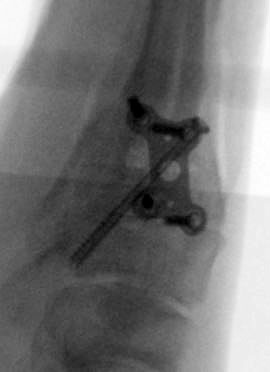

Abbildung 15a

Abbildung 15b

Abbildung 18a

Abbildung 18b

Direkt postoperativ Röntgenkontrolle (Fuß in zwei Ebenen). Sechs Wochen postoperative Röntgenverlaufskontrolle in zwei Ebenen im Stehen. Ist die Überbauung der Arthrodese nicht gut zu beurteilen, kann eine ergänzende 45° Supinationsaufnahme des Fußes angefertigt werden, die einen guten Einblick in das Tarsometatarsale-I-Gelenk ermöglicht.